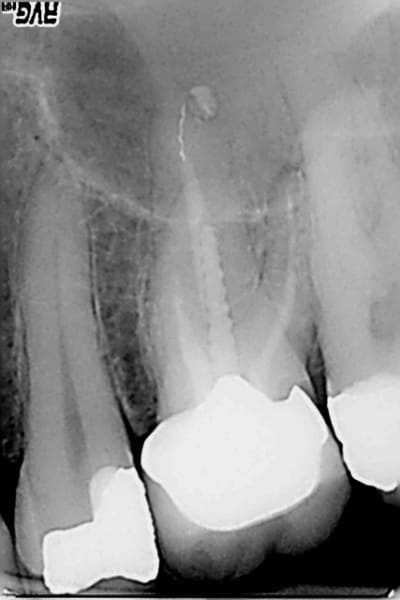

Ceram à refaire sur cette 26 facile : dépose , rectification de préparation empreinte, provisoire ( 20 mn) et pose. Sauf que le sc 33 initial est resté dans la provisoire à la dépose de celle ci.-))

Pas grave j' y ai recollé un screw post titane (screw pol de chez apol) avec du mimesis DC ( composite dual multi usage) après avoir apprêté l'intrados de la couronne et le reste de la dent au peak universal bond.

Voilà, pas de signe d'appels, la plus stricte économie, pas de signes radios 2D (lol!) et cerise sur le gateau une seule radio post op, gestion en bon père de famille comme ca pas besoin de se rattraper sur la prothèse -))))

Je ne voudrais pas jeter de l'huile sur le feu mais ce qui me gène le plus n'est pas l'éventuelle pêche sur la racine palatine mais plutôt que sur la radio de contrôle la couronne n'est même pas en place avec un hiatus en mésial et une marche en distal.

ça veut dire que le pauvre patient va inéluctablement perdre sa dent dans un délai relativement court soit par carie sous gingivale, soit par problème paro sans parler du manque d'étanchéité du composite et de la perte du point de contact distal.

Edit: et j'avais même pas vu la photo avec la pointe du tenon noircie par la percolation bactérienne dans le canal palatin ... effectivement pas besoin de RTE.

1. Ne pas se fier aux radios dont les images dépendent de l'incidence.

Le soucis, dans le cas présent, est qu'il y aura surement un abcès dentaire dans moins de 2 ans sur cette dent... Du moins c'est fort probable.

Ce gros screw post en se descellant a surement rompu un équilibre précaire qui faisait que cette obturation canalaire médiocre au demeurant n'avait pas déjà eu pour conséquence un joli granulome.

En l'occurence, le reste de gutta du canal a surement été descellé aussi au cours de la manœuvre.

Et cela aboutira dans quelques mois à ce qui est communément appelé une pêche...

Je trouve juste que tu as pris un risque sur ce coup là. Autant, je suis contre le retraitement systématique (quand il n'y a pas de symptôme), autant lorsque je me retrouve dans le canal et qu'il est mal obturé radiologiquement parlant, je pense que pour être plus serein, il vaut mieux retraiter...